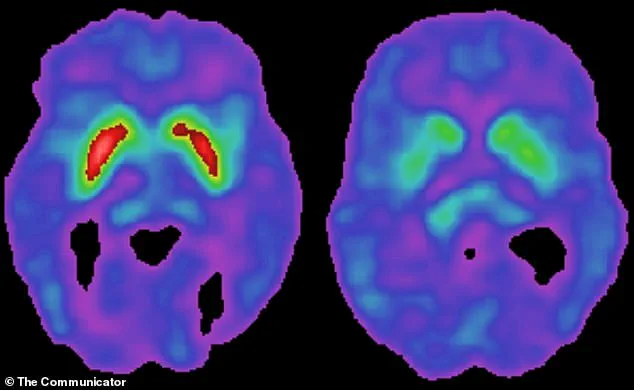

Patients infected with the virus exhibited more advanced brain damage, including significant degeneration of dopamine-producing neurons, which are critical for motor control.

This combination triggered an inflammatory cascade in the brain, which damaged and killed neurons, particularly the dopamine-producing cells in the substantia nigra—a hallmark of Parkinson’s disease.

Parkinson’s disease is characterized by the degeneration of dopamine-producing neurons in the substantia nigra.

Dopamine is critical for both the brain’s reward system and movement control.

When levels drop, the brain’s movement circuits become impaired, leading to stiffness, tremors, and difficulty initiating movement.